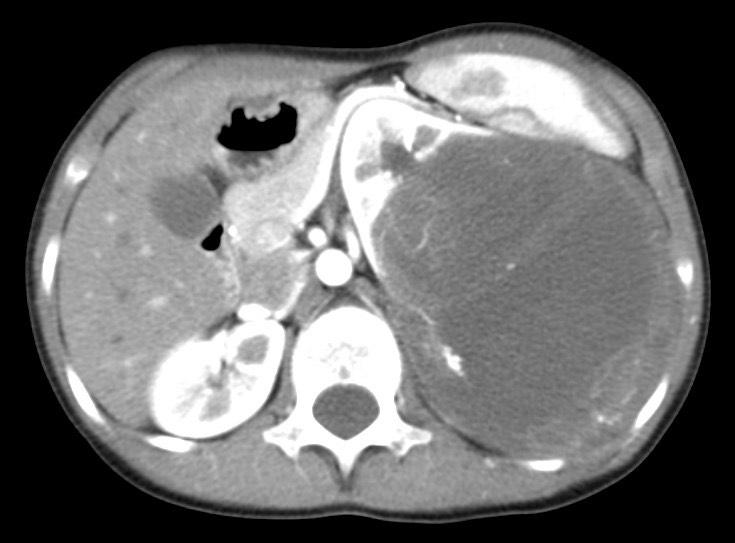

1386. Пациенту 8 лет с болями в левом боку в подреберье, интермиттирующей лихорадкой до 38,8⁰с проведено обследование и антибиотикотерапия, вследствие которых боли купировались, но сохранилась субфебрильная лихорадка, выполнили компьютерную томографию, патологическим процессом считают